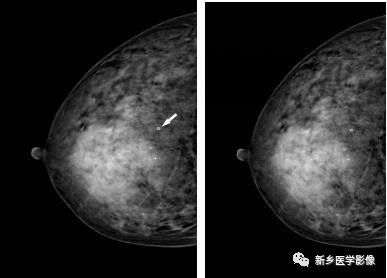

乳腺良性肿块X线图像

右乳CC位片示肿块圆形,边缘光滑、清晰,见透亮线环绕(白箭)

乳腺恶性肿块X线图像

a. 左乳CC位和b. MLO位片示肿块边缘分叶状,见数个长毛刺,周围血管增粗(白箭)